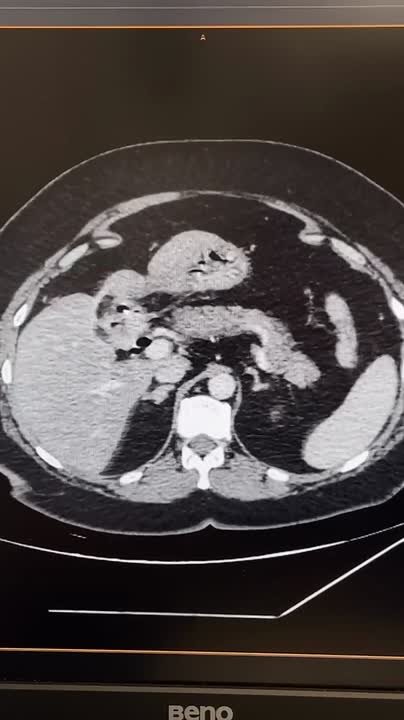

Для уточнения диагноза врачи выполнили МСКТ с контрастированием и обнаружили инородное тело в верхних отделах тонкой кишки, желчный пузырь не визуализировался. По словам пациентки, до этого операций на животе у нее не было. Специалисты предположили миграцию камня из желчного пузыря в кишечник с формированием пузырно-двенадцатиперстного свища. Диагноз подтвердила ФГДС.